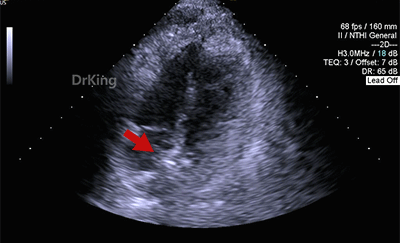

超声检查

房间隔中部有回声中断,测ASD大小:8×8×9mm,CDFI探及左向右分流,距主动脉根部0mm,距二尖瓣环10mm,距房顶14mm,距上腔静脉13mm,距下腔静脉11mm。

心脏彩超提示:先天性心脏病:房间隔缺(继发孔型)。右室稍增大。左心室收缩及舒张功能正常。右心室收缩功能正常。下腔静脉瓣冗长。